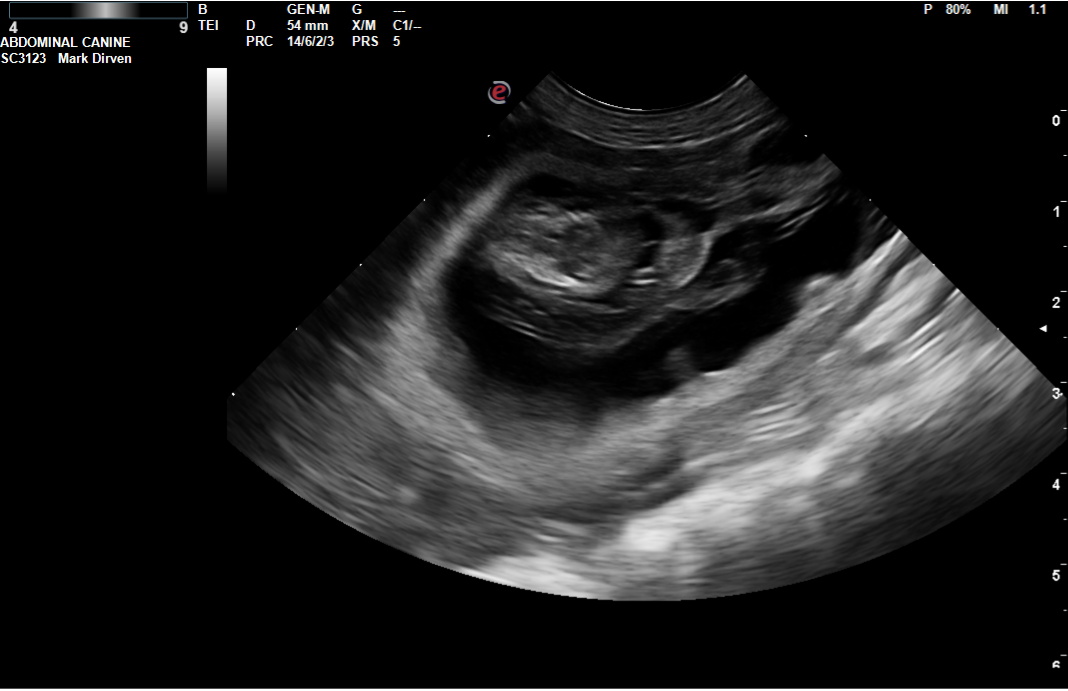

De pups zijn echt flink aan het groeien en daardoor krijgen ze minder ruimte in de buik. Daardoor zijn de pups nu goed te voelen. Zeker als de moeder rust kan je het momentje pakken. Vanaf dag 57 kunnen de pups zonder problemen ter wereld komen.